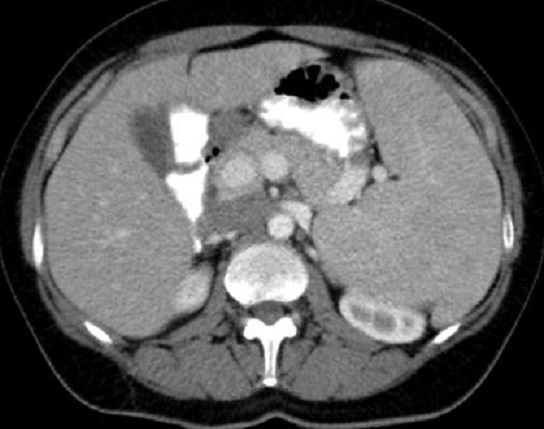

Aspect lesionelle

de micronodulaire diffuse de taille variable de 2-4mm à

hypodense d'une lymphome maligne de la rate . Image

radiologique TDM plus C+ de contrast

phase veineuse , coupe axial |